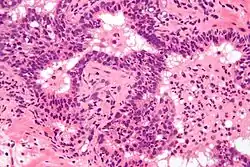

Prostate biopsies are not indicated as the (clinical) features (described above) are diagnostic. The histologic correlate of acute prostatitis is a neutrophilic infiltration of the prostate gland.